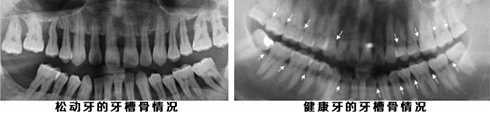

牙周病发展至较为严重的程度,大多数会发生“牙齿松动”。其特点是牙周组织广泛破坏,同时出现溢脓,牙龈出血,红肿疼痛,牙齿松动,口臭等症状。

特别提醒:>sp>an不要盲目拔牙,拔牙前需拍摄全景的口腔CT片(江苏仅淮安市口腔医院可提供口腔全景CT拍摄),明确牙齿确实没有存在的价值后再进行拔出!此外,因文章内容阐述有限,不能将每个人的疑问一一解决,如有疑问或想提前预约不排队,可点此sp>an>a或sp>an>a,也可直拨打就诊热线:sp>an 。